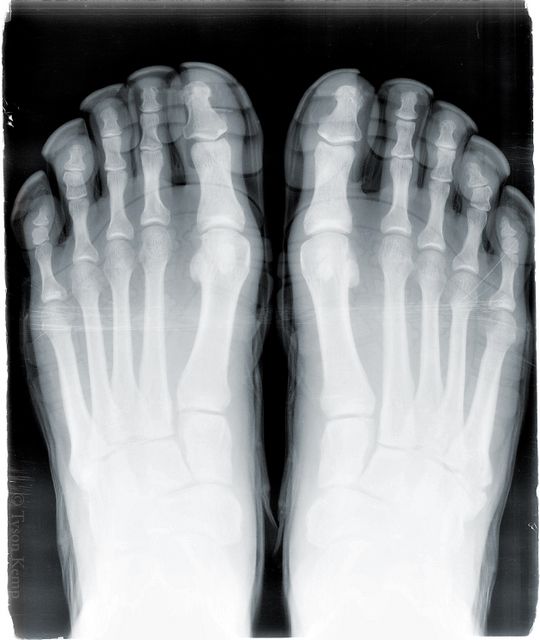

X-Rayed Vibram Five Fingers KSO Treks

<a href="/a> Fan, Tyson, recently went in to have his foot checked and left with an x-ray of his foot. Oh, his foot was still in his KSO Treks! Tyson gives us the run down:

I went in because I've had pain on the outside of my right foot for some time from an old injury that may have involved parkour amongst other things. I've noticed since I've been using my KSO Treks that the pain has subsided and I wanted to see what was going on there. My main foot man, Rich said, "Well let's take a look with an x-ray". That was the point when he noticed them. He didn't know what to think of the "gloves on my feet". So, I asked if I could get an x-ray with my Five Fingers on. He said, "Sure, I'll just burn it to a CD for you". Whatever that is, lol. So, when he looked the x-ray, he noticed that the pain was from a small extra bone I have just right there. He thought it was maybe an on going fracture. but now it maybe tendinitis from this extra bone. I can't help but give some credit to these shoes.

Glad to hear you are finding some relief in your KSO Treks and thanks for the cool pic!